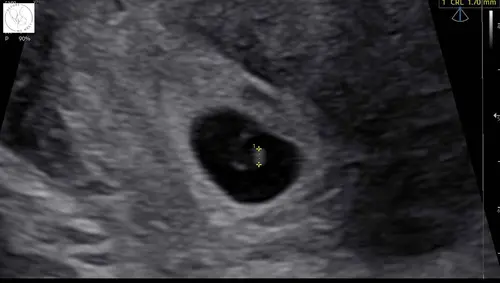

Echo met 5+4. Hartje al zien kloppen volgende echo met 8 weken of waar die ...